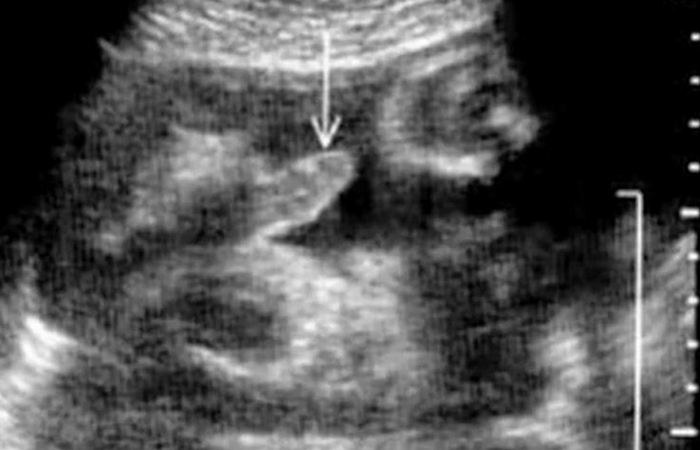

2. Эрекция у плода

Беременность: эрекция у плода в утробе матери.

Подавляющее большинство матерей даже не знает о том факте, что у мальчика у них в утробе во время беременности может случиться… эрекция. Более того, известно, что дети обоих полов мастурбируют в утробе матери. Пожалуй, понятно, почему врачи умалчивают об этих шокирующих фактах.